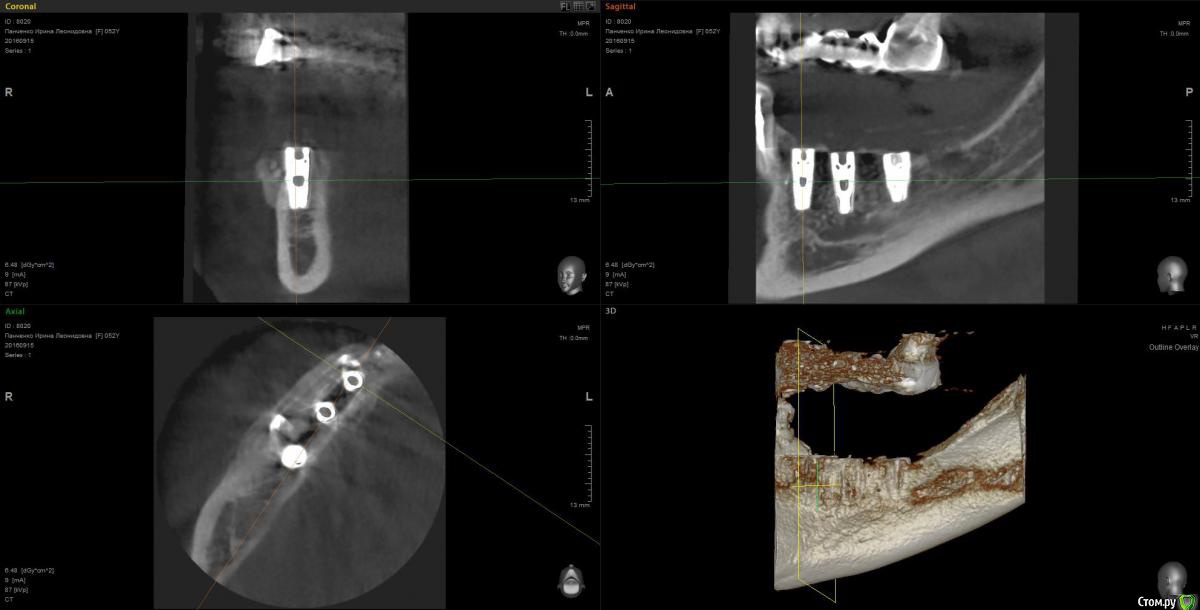

Kostoprav Опубликовано 13 марта, 2017 Поделиться Опубликовано 13 марта, 2017 рецепт сосиски: 70%биопласт by владмива +30%аутокость, мембрана hyprosorb кт до кт сразу после имплантации кт через пол года 3 Ссылка на комментарий